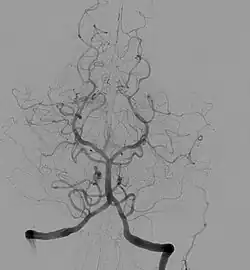

![]() La arteria basilar (centro de la figura) nace de la confluencia de las arterias vertebrales y termina cuando se bifurca en las arterias cerebrales posteriores derecha e izquierda. | ||

Nace en la confluencia de las dos arterias vertebrales a la altura de la unión de la médula oblonga (o bulbo raquídeo) con el puente troncoencefálico.

Asciende en el canal central (surco basilar) inferiormente al puente troncoencefálico y se divide en las arterias cerebrales posteriores ACP(derecha e izquierda) y la arteria cerebelosa superior ACS justo por debajo del infundíbulo de la hipófisis.

De la arteria basilar nacen la arteria cerebelosa inferior anterior ACIA, que irriga las regiones superior e inferior del cerebelo, así como ramas más pequeñas que irrigan el puente troncoencefálico, las arterias o ramas pontinas.